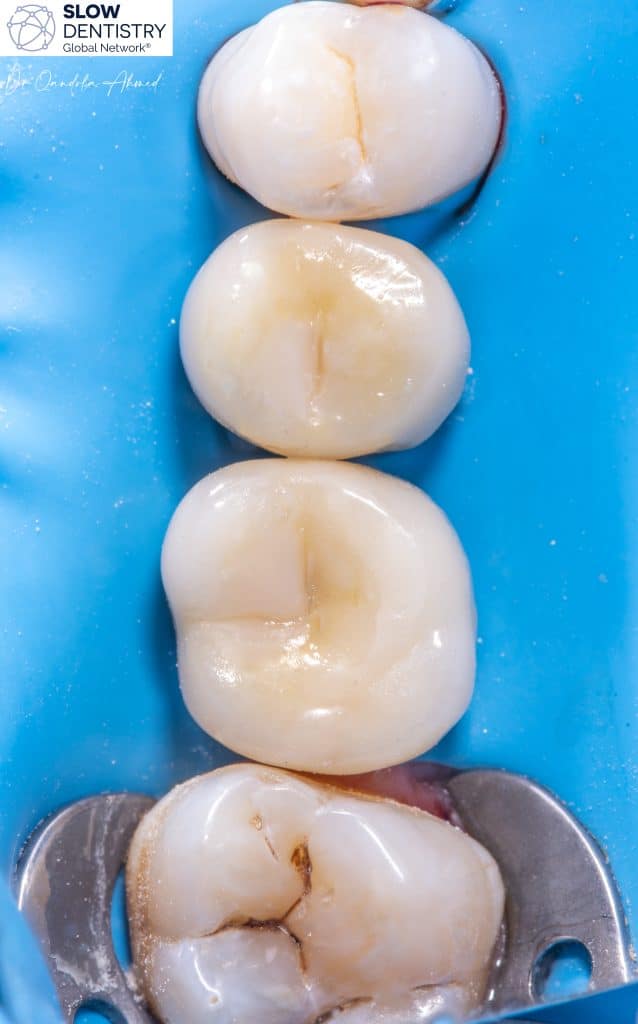

When considering the question of whether dental implants should be separated or splinted, it is essential to weigh the advantages and disadvantages of each approach.

At least one reason pushes to finalize multi unit implant case with seperated crowns is Independent Load Distribution !

Separating dental implants allows for independent load distribution. Each implant functions as a standalone unit, distributing occlusal forces individually. This reduces stress on the supporting bone and minimizes the risk of overloading any specific implant.